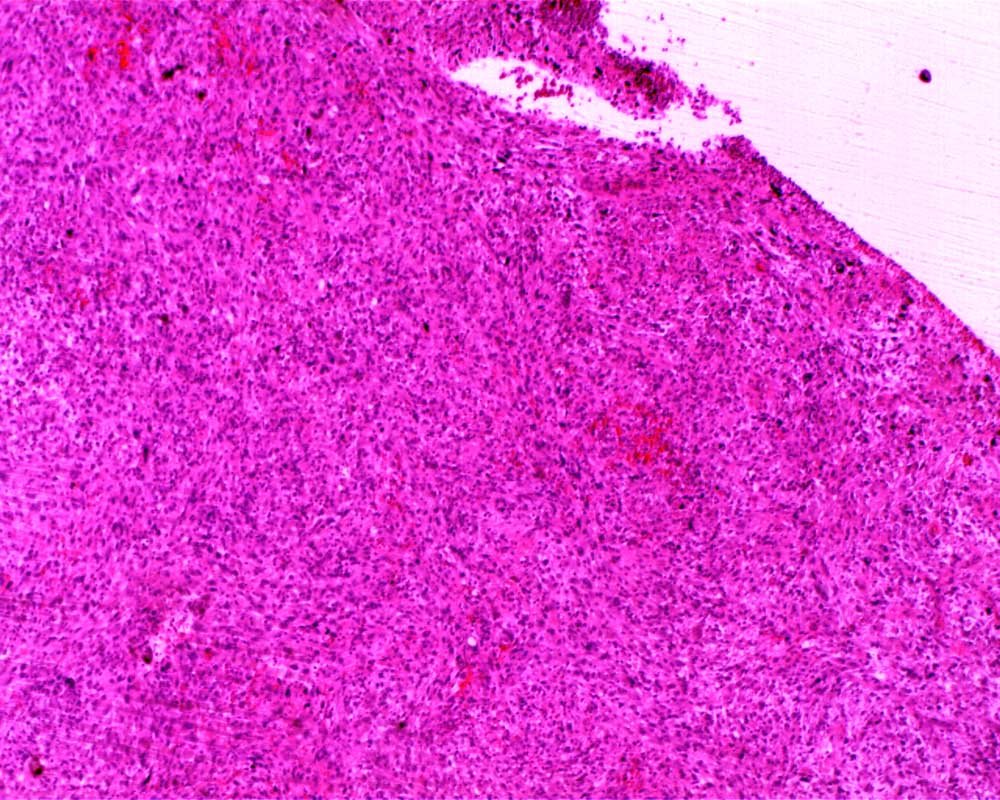

Case: LegMass

Final Diagnosis: